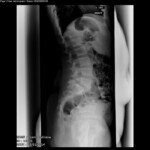

Ἡ νόσος εἶναι ἐπίκτητος, στὴν Εὐρώπη δὲ ἀφορᾶ δὲ τὸ 5% τῶν ἐνηλίκων καὶ 2% τῶν ἐφήβων καὶ παιδιῶν. Οἱ στατικὲς συνέπειες τῆς σπονδυλύσεως-σπονδυλολισθήσεως εἶναι: Ἐξάλειψη τῆς φυσιολογικῆς ὀσφυϊκῆς λορδώσεως ἢ καὶ μετατροπή της σὲ ὀσφυϊκὴ κύφωση (εἰκ. 8), ἐξάλειψη τῆς φυσιολογικῆς θωρακικῆς κυφώσεως, ἐλαττωμένη εὐλυγισία κινήσεων τῆς λεκάνης, μετατόπιση τοῦ κέντρου βάρους τοῦ σώματος πρὸς τὰ πρόσω (κοιλιακά), ἐλάττωση τοῦ ὕψους τοῦ κορμοῦ. Ἐντυπωσικὸ ὅμως εἶναι ὅ,τι σὲ ὄχι εὐκαταφρόνητο ἀριθμὸ παιδιῶν δὲν ὑφίστανται ἀρχικῶς συμπτώματα, παρὰ τὰ τυπικὰ ἀκτινολογικὰ εὑρήματα. Μὲ διαρκῆ ὅμως παρουσία τῆς νόσου, ἀρχίζουν σταδιακὰ νὰ ἀναφύονται καὶ τὰ ἀναμενόμενα συμπτώματα. Τὸ κυρίαρχο σύμπτωμα εἶναι πόνος κατὰ τὴν διάρκεια κάποιων κινήσεων, πόνος ποὺ ἔχει ζωστηροειδῆ περὶ τὴν ὀσφὺ ἐπέκταση καὶ μὲ φορὰ ἀπὸ πίσω πρὸς τὰ ἐμπρός, εἰδικὰ τὸ πρωῒ, ὅταν οἱ μῦες τῆς ράχεως εἶναι χαλαροί. Ὑπάρχει ἐπίσης ἕνα αἴσθημα ἀστάθειας στὴν Σ.Σ.. Σὲ σοβαρὲς περιπτώσεις παρατηρεῖται ἀπώλεια ἀντανακλαστικῶν, ὑπαισθησία κάτω ἄκρων καὶ διαταραχὲς κινητικότητος. Τότε ἡ χειρουργικὴ θεραπεία (εἰκ.9) εἶναι μονόδρομος! Σὲ γενικὲς γραμμὲς τὰ συμπτώματα προσομοιάζουν μὲ ἐκεῖνα τῆς κήλης δίσκου (δισκοπάθεια).

Ἡ διεθνὴς ταξινόμηση τῶν σταδίων τῆς σπονδυλολισθήσεως ἀκολουθεῖ τὸν ὑποδειχθέντα ὑπὸ τοῦ Meyerding κανόνα, σύμφωνα μὲ τὸν ὁποῖο τὸ μῆκος τῆς ὀλισθήσεως ἑνὸς σπονδύλου εἶναι συνάρτηση τοῦ μήκους τῆς βάσεως τοῦ ὑποκειμένου σπονδυλικοῦ σώματος. Ἡ διάγνωση ἢ ἡ ὑποψία μιᾶς σπονδυλολύσεως καὶ κατὰ τὶς περιστάσεις τῆς σπονδυλολισθήσεως τίθεται μὲ μία πλαγία ἀκτινογραφία ΟΜΣΣ καὶ μὲ ἐπικέντρωση στὸ ὕψος Ο4-Ο5-Ῑ1. Ὀριστικὴ ἐπιβεβαίωση δίδεται διὰ τῆς διενεργείας λοξῆς (45ο) ἀκτινογραφίας, ὅπου ἡ ἀπεικονιζόμενη σπονδυλόλυση περιγράφεται συχνὰ μὲ τὸν ἀποδοθέντα ὑπὸ τῶν παλιῶν ἀκτινολόγων ὑπέροχο ὅσον καὶ γλαφυρὸ ἀκτινολογικὸ ὅρο: «ἡ φιγούρα τοῦ σκύλου μὲ τὸ κολλάρο» Τὸ κολλάρο τοῦ σκύλου εἶναι ἡ διαυγαστικὴ γραμμὴ τοῦ ρωγμώδους κατάγματος τοῦ σπονδυλικοῦ τόξου!! (Οἱ εἰκ. 10,11,12 καὶ 13) ἀκριβῶς παρουσιάζουν τὴν 4ετῆ πορεία ἑνὸς κοριτσιοῦ , ποὺ σὲ ἠλικία 10 ἐτῶν, ὑπέστη σπονδυλόλυση καὶ σπονδυλολίσθηση τοῦ Ο5 ἐπὶ τοῦ Ι1 κατὰ τὴν διάρκεια ἀσκήσεως μοντέρνου χοροῦ. Χαρακτηριστικὴ εἶναι ἡ ὕπαρξη τοῦ ἀκτινολογικοῦ κριτηρίου «τῆς φιγούρας τοῦ σκύλου μὲ τὸ κολλάρο»!!) Ἐὰν τὰ εὑρήματα στὶς ἀκτινογραφίες δὲν εἶναι σαφῆ, ἐπιβάλλεται περαιτέρω ἔλεγχος μὲ μαγνητικὴ τομογραφία.

Σημ.: οἱ εἰκόνες 10, 11, 12, 13 καὶ 14 προέρχονται ἀπὸ τὸ ὑλικὸ ἀρχείου τοῦ ἐργαστηρίου μου.